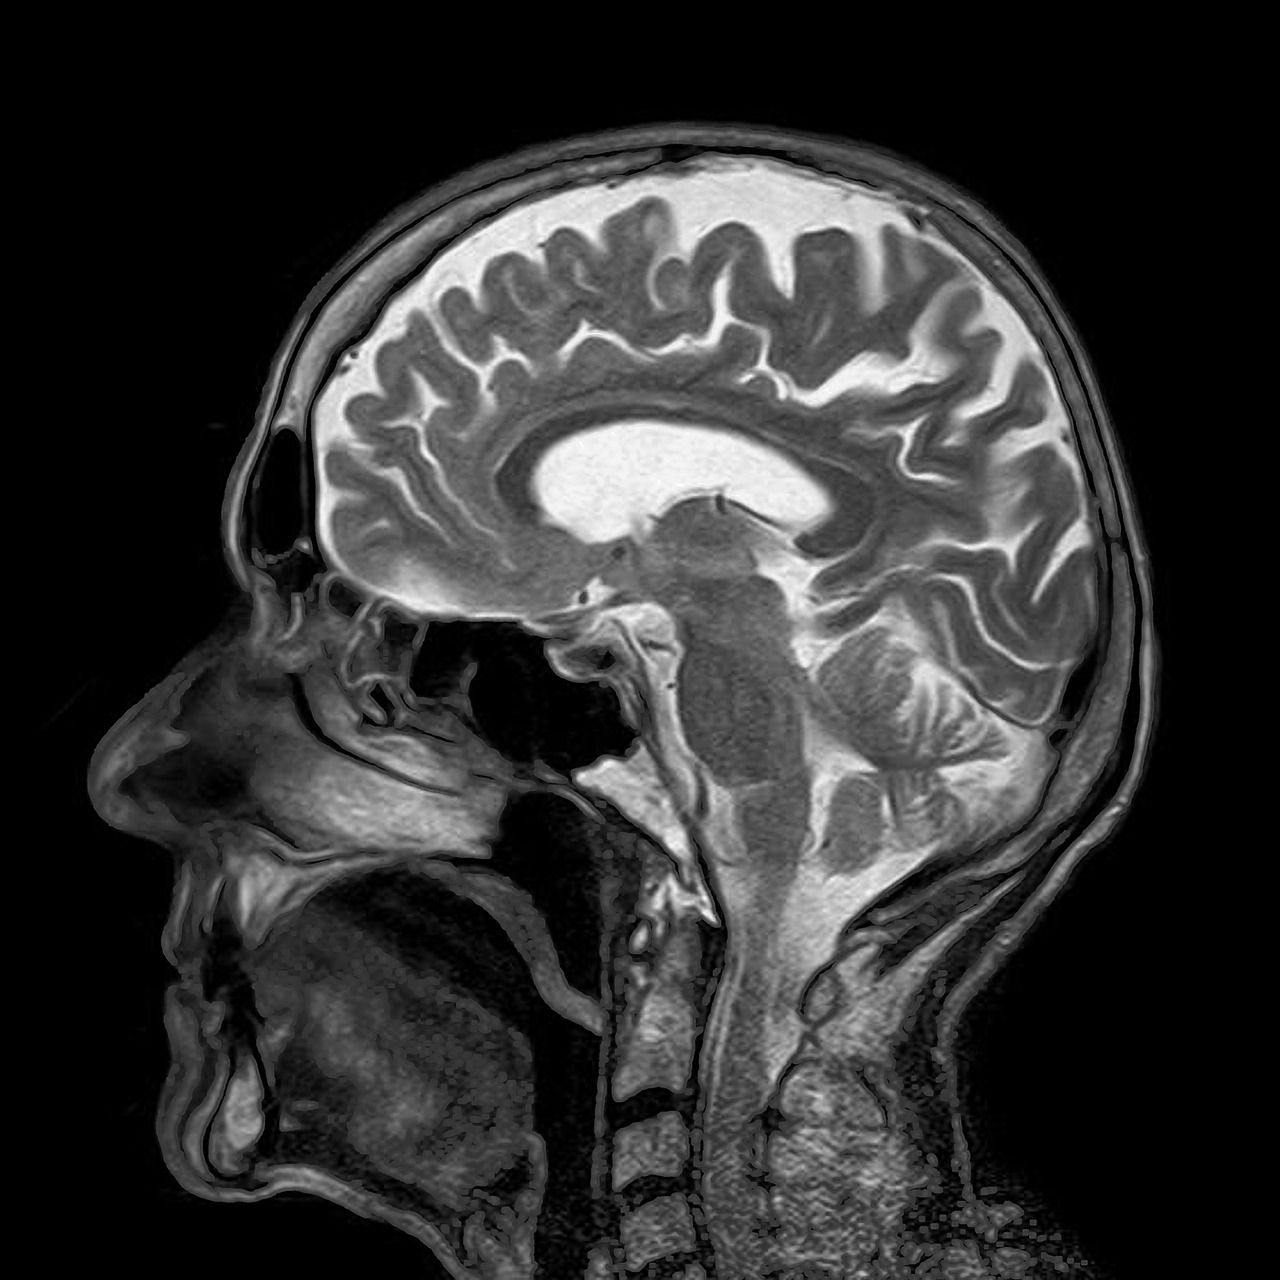

To give you an example, below I’ve inserted three models of the same thing: a nucleosome. Each of these was clearly developed to emphasize a particular relationship between structure and function. But those relationships lie at different scales, which has dictated the level of detail that is included, what lies in the foreground and background, and influenced all sorts of stylistic decisions.